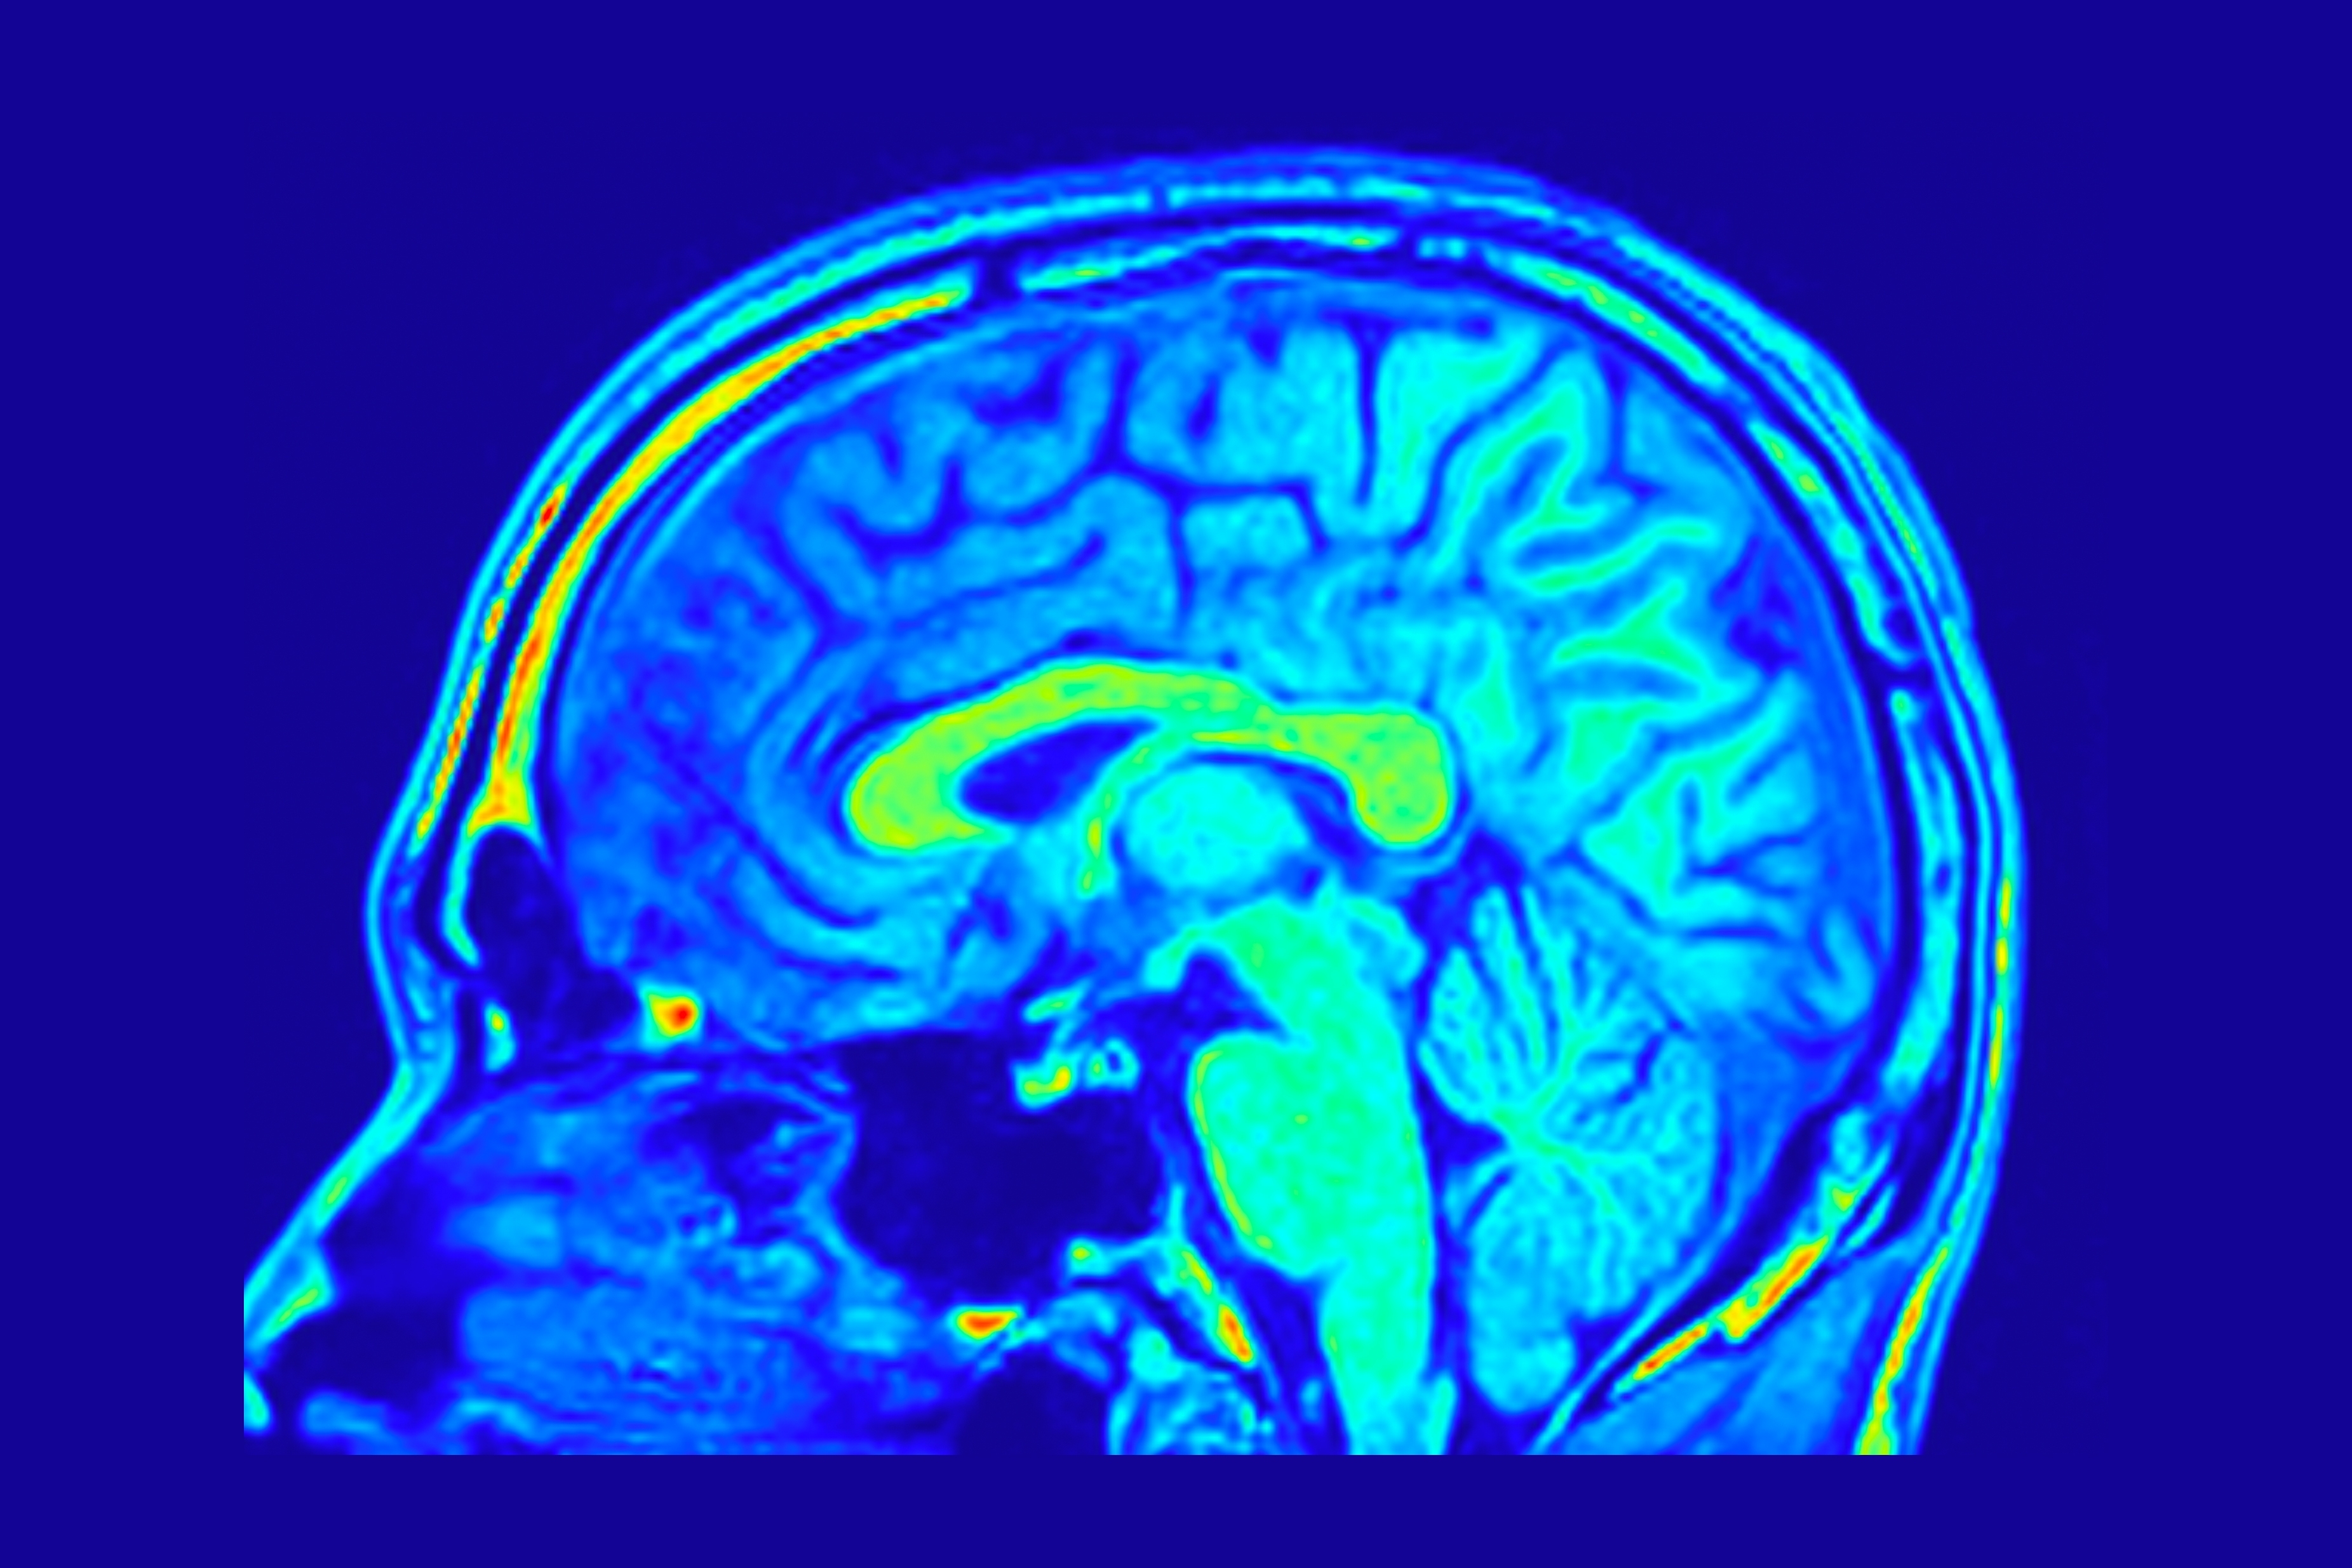

Plasma and neuroimaging biomarkers of small vessel disease and Alzheimer’s disease in a diverse cohort: MESA

Alzheimer’s & Dementia, December 2025

Authors:  Samuel N. Lockhart1, Courtney L. Sutphen1 Jordan Tanley, Fernando Gonzalez-Ortiz, Przemysław R. Kac, Mohamad Habes, Susan R. Heckbert, Nicholas J. Ashton, Michelle M. Mielke, Robert Koeppe, Marc D. Rudolph, Kiran K. Solingapuram Sai, Christopher T. Whitlow, Kevin D. Hiatt, Suzanne Craft, Thomas C. Register, Kathleen M. Hayden, Stephen R. Rapp, Bonnie C. Sachs, Henrik Zetterberg, Kaj Blennow, Thomas K. Karikari, Timothy M. Hughes